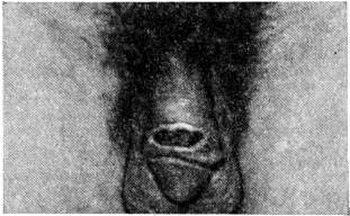

Рис. 3.

Язва на крайней плоти полового члена при паховом лимфогранулематозе.

Клиническая картина. Инкубационный период 1½ — 2 недели. В типичных случаях заболевания различают три последовательных периода. Первичный (лимфогранулематозный шанкр): на месте внедрения возбудителя, то есть в области половых органов (возможно экстрагенитальное поражение — губы, полость рта, язык и другие), возникает единичный пузырёк (реже папула), быстро трансформирующийся в эрозию, а затем в язву диаметром до 1—3 см неправильных округлых или овальных очертаний, неглубокую, с неровным дном (рисунок 3), покрытую гноем серовато-тусклого, иногда желтовато-зеленоватого оттенка. Типично наличие островоспалительного ободка и отсутствие характерного для твёрдого шанкра (смотри полный свод знаний Сифилис) уплотнения в основании. Обычно через 7—9 дней на фоне намечающейся тенденции язвы к самопроизвольному заживлению наблюдается постепенное увеличение, уплотнение и болезненность регионарных лимфатических, узлов (у мужчин чаще паховых, у женщин — малого таза).